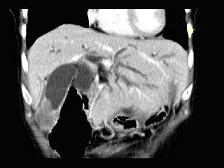

问题 患者,男,51岁,右上腹隐痛两月余,CT扫描如图,最可能的诊断是()

选项 A.胆囊癌伴肝门胰头周围转移 B.胆囊息肉 C.胆囊黄色肉芽肿 D.慢性胰腺炎并胆囊息肉 E.胆囊腺瘤及慢性胰腺炎

答案 A